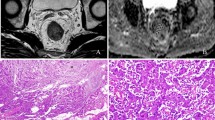

Histological assessment and correlations with ADC and DKI-derived parameters

The mean cell count of CRC/EMT tumors was 700 ± 43 (range, 650–774), which was significantly higher than that of 488 ± 42 (range, 428–553) in CRC/Control tumors. Both ADC and diffusivity showed negative correlation with tumor cellularity (r = −0.47, P = 0.036 vs. r = −0.56, P = 0.010). Kurtosis demonstrated positive correlation with tumor cellularity (r = 0.74, P < 0.001). Compared with CRC/Control tumors, the CRC cells showed poorer differentiation and more heterogeneity with spindle-shaped alternation (Fig. 4A and B), down-regulation of E-cadherin expression (Fig. 4C and D), and higher Ki-67 expression in CRC/EMT tumors (Fig. 4E and F). Correlations between the diffusion parameters and immunohistochemical indexes were shown in Table 3. There was no significant correlation between ADC and E-cadherin expression (P = 0.068). Diffusivity was negatively correlated with Ki-67 expression (P = 0.007) and positively correlated with E-cadherin expression (P = 0.023). Kurtosis was significantly positively correlated with Ki-67 expression (P < 0.001) while it was significantly negatively correlated with E-cadherin expression (P = 0.006).

Hematoxylin and eosin (HE) and immunohistochemical analysis of representative CRC/Control and CRC/EMT tumors. The left and right columns were representative images of HE, E-cadherin, and Ki-67 staining for the CRC/Control and CRC/EMT tumors. HE staining showed that CRC/EMT cells were more heterogenenous with spindle-shaped alteration (B, 200× , arrow) compared with the CRC/Control (A, 200×). Immunohistochemical stainings showed that E-cadherin expression (D, 200× , arrow) was repressed, and positive Ki-67 expression (F, 200×, arrow) was higher in the CRC/EMT group as compared with the CRC/Control (C, 200× , arrow; E, 200×, arrow)